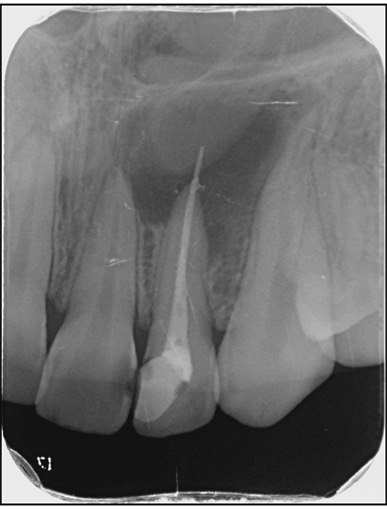

1. What Condition can be seen in this X ray regarding the tooth # 1.1.?